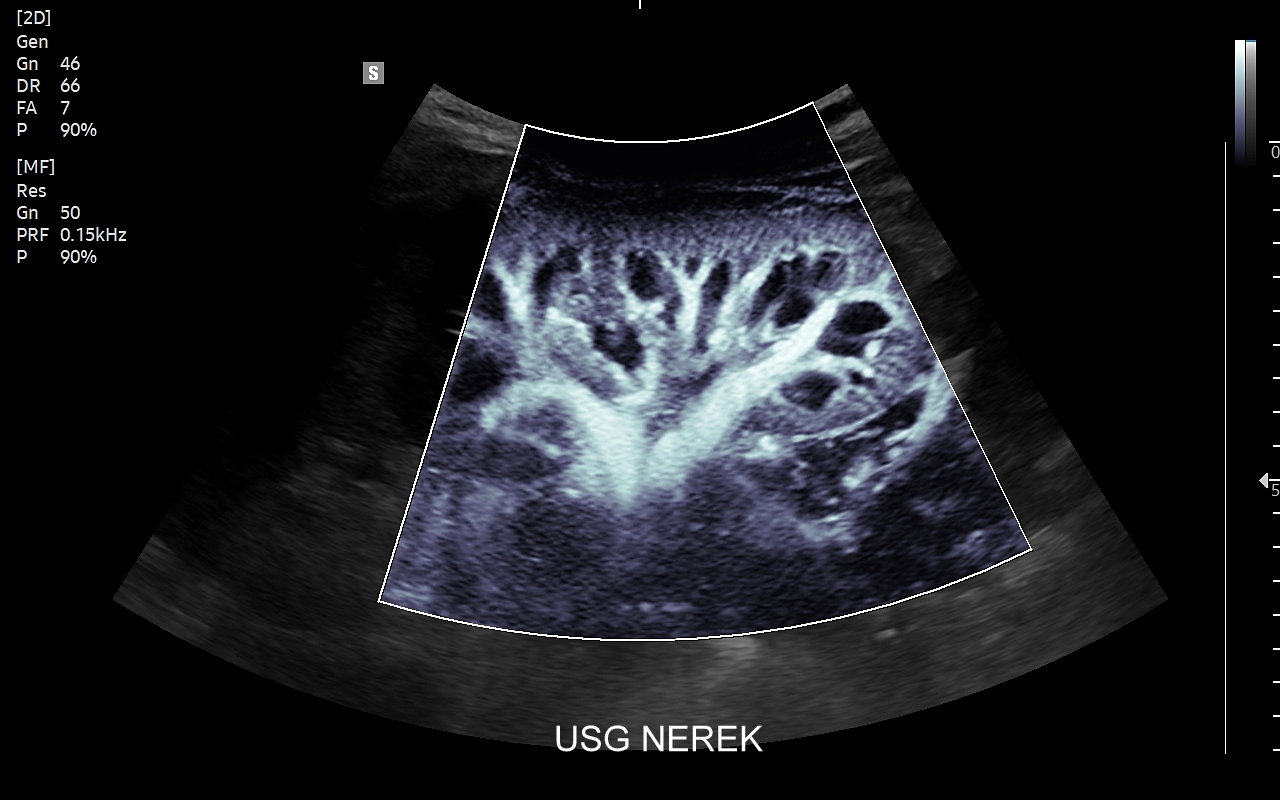

• w 2015 r. wprowadził do użycia badania dopplerowskie w diagnostyce cukrzycy i ocenie niewydolności nerek;

Dr Tomasz Szczepański zajmuje się kompleksową opieką medyczną nad swoimi Pacjentami. W ramach Interdyscyplinarnej Pracowni USG Wrocław wykonuje szereg uzupełniających się badań, zarówno klasycznych, jak USG jamy brzusznej, USG tarczycy, USG piersi, pełen zakres diagnostyki USG Doppler, jak i wysokospecjalistycznych, w tym badania multiparametryczne (MPUS), badania USG z kontrastem (CEUS), ocena przetok dializacyjnych, badania USG Doppler przepływów nerkowych, czy badania USG twarzy